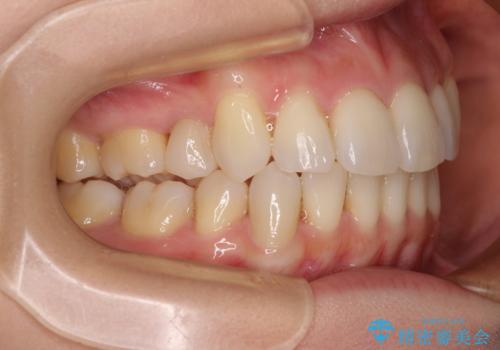

右側の上下は歯が重なり合って、内側に移動してしまうほどであり、それに伴って正中の位置が右側にずれている状態でした。